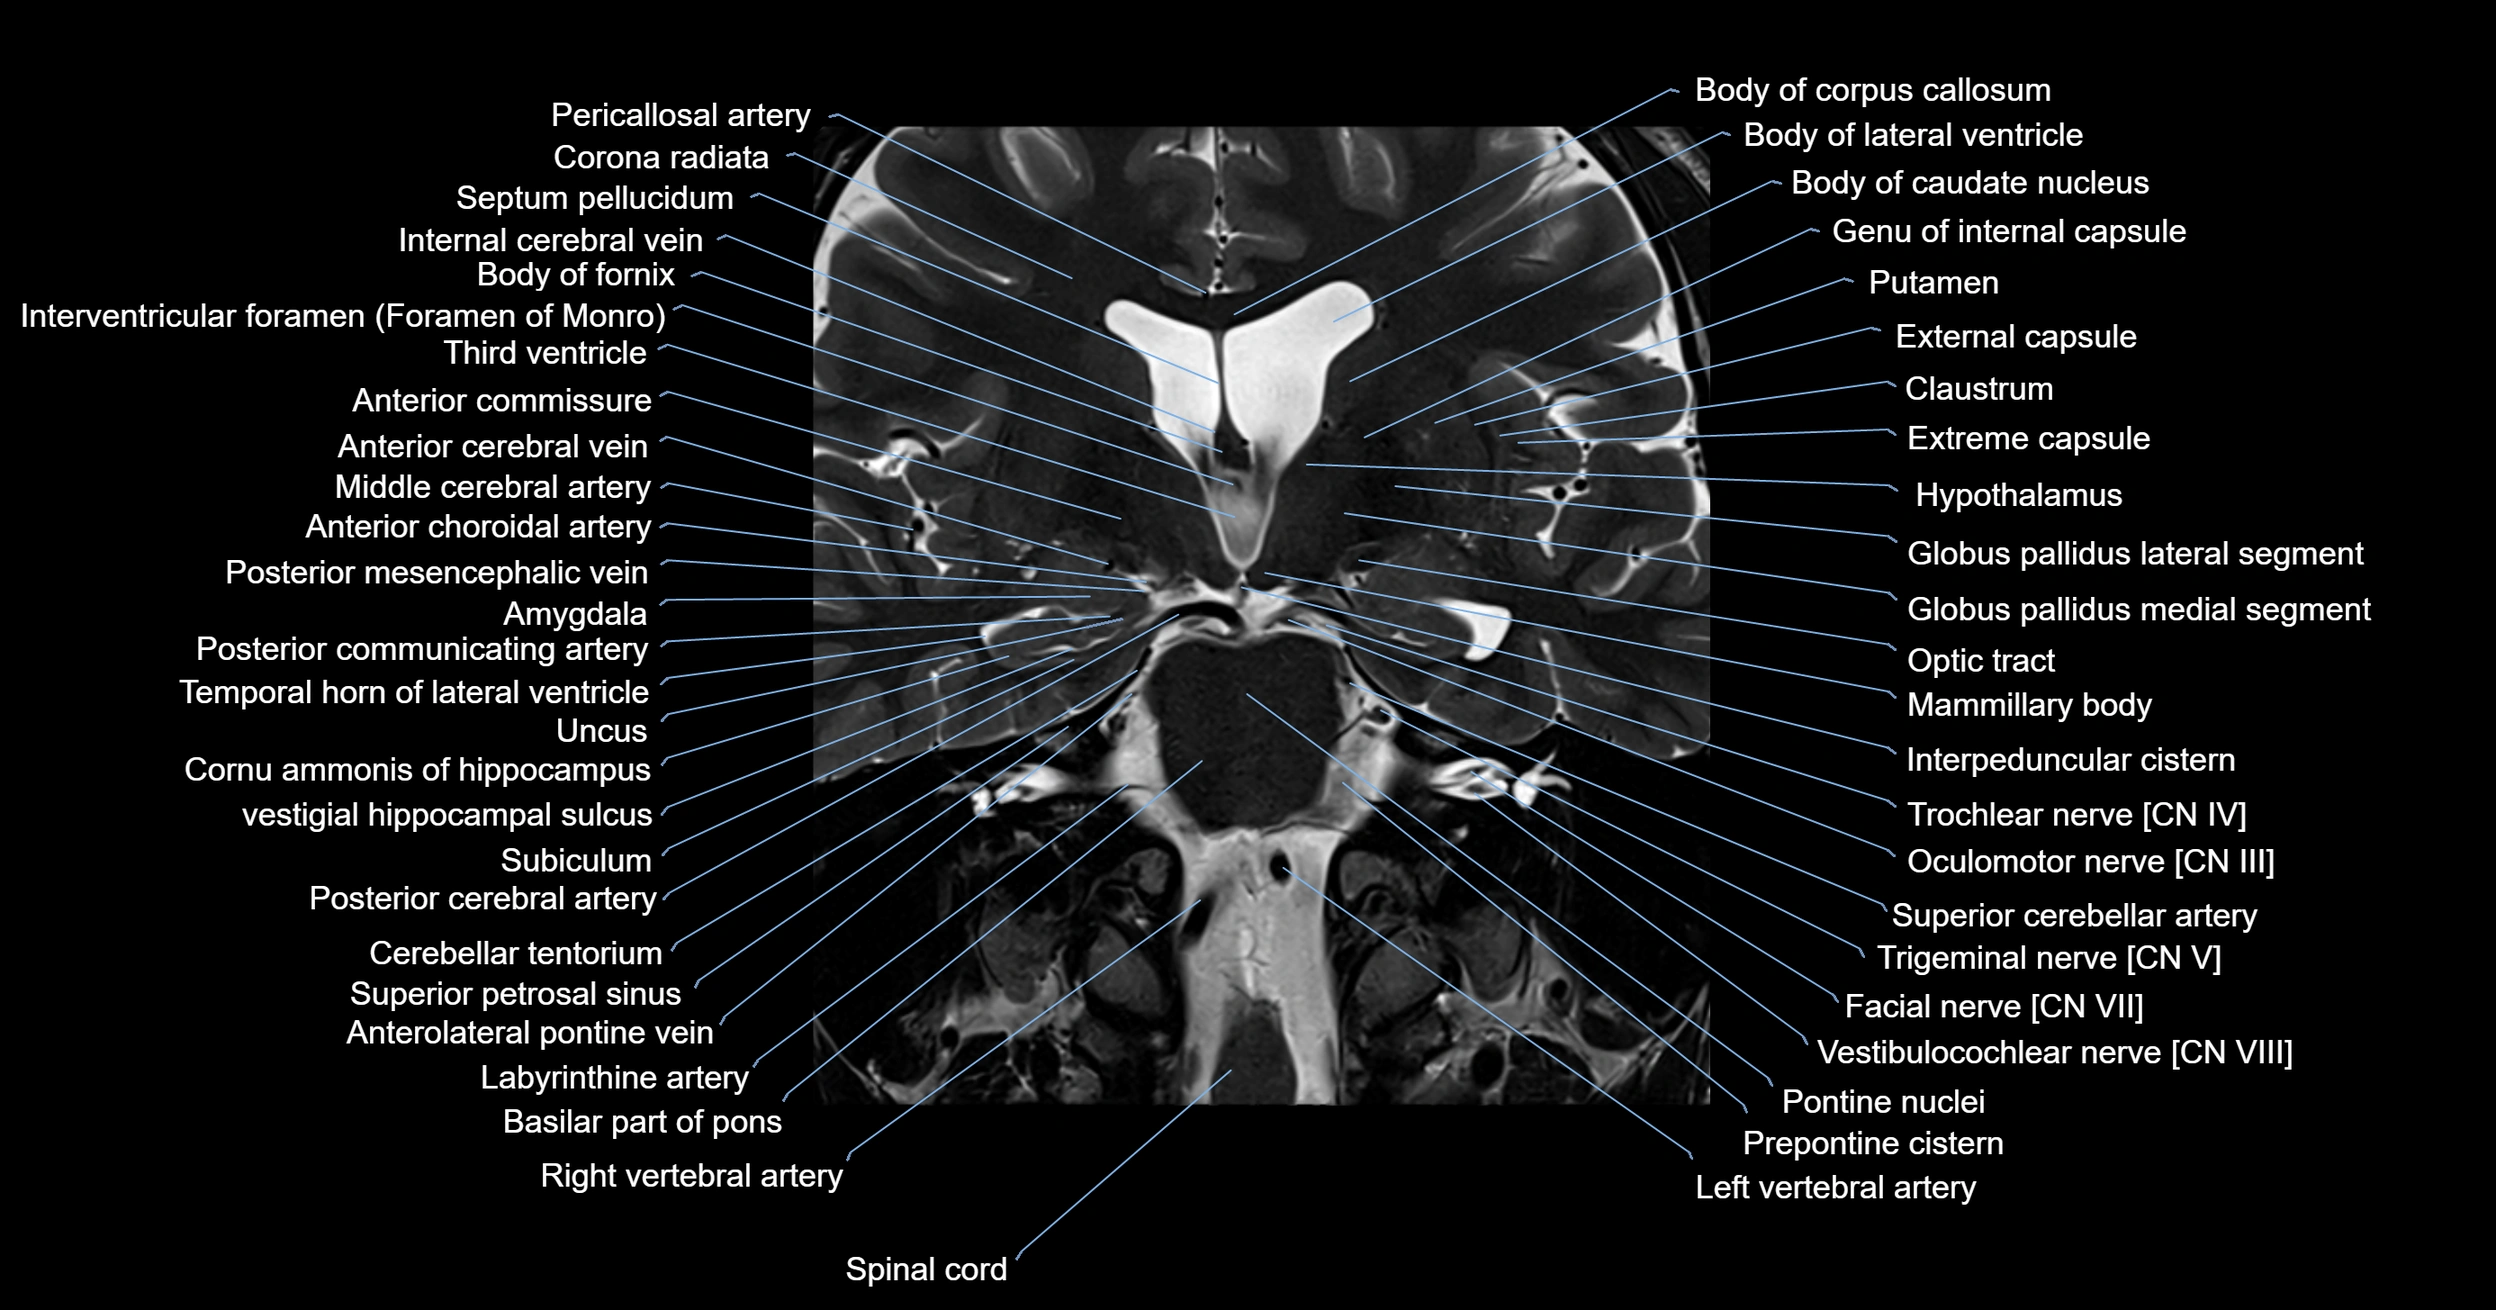

MRI images